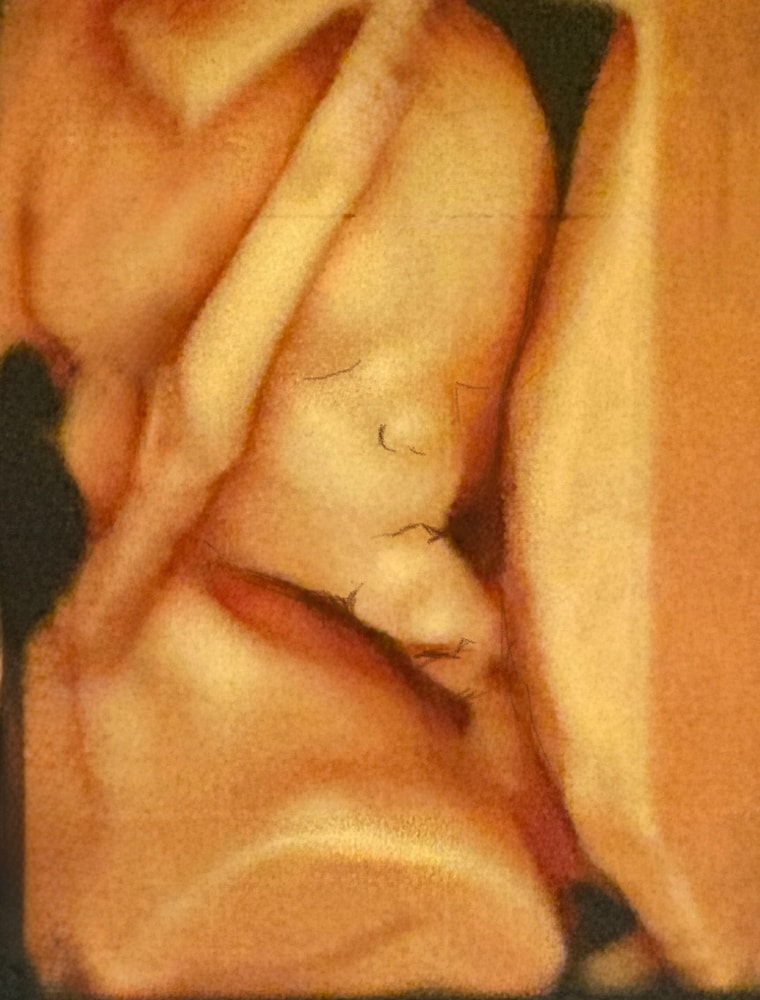

Привет из космоса!

Началась 15 неделя

Вышли с портретом) Человек весит почти 100г

Плацента сбоку справа, перекрывает зев на 2.2 см.

Шейка 32.2

Какой сладкий мальчишка! Пальчик сосет 🥰